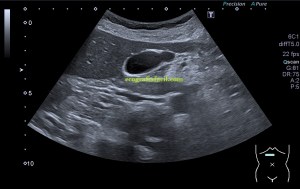

Durante la exploración de una eco de abdomen en el contexto de un paciente que acude por elevación de transaminasas observo una imagen heterogénea, irregular, con una pared marcadamente calcificada, bilobulada de gran tamaño que medí en dos partes ya que me pareció claramente que estaban diferenciadas.

Una de ellas, la primera, era mucho más hiperecogénica y más pequeña, su centro estaba mas calcificado, su sombra acústica posterior era mucho más acuciada y llamaba más la atención. Justo al lado, otra lesión de mayor tamaño, su calcificación era mucho más sutil y más periférica delimitando una LOE hipoecogénica de un tamaño muy importante, adyacente a la más pequeña, como he comentado previamente. Ambas sin señal Doppler.